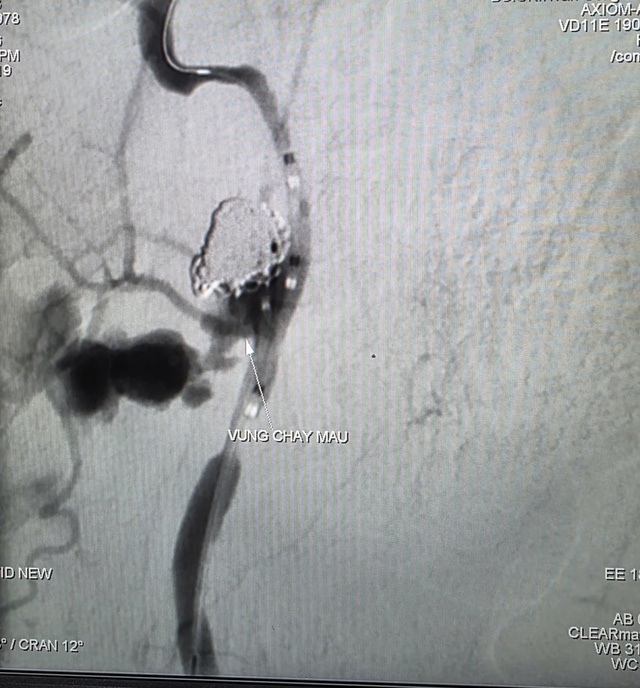

Hình ảnh thoát mạch trước can thệp

Kết quả CT Scan ghi nhận tổn thương vùng dạng khối choán chỗ khoang niêm mạc hầu lệch phải, xâm lấn vào động mạch cảnh trong tương ứng, có dấu hiệu thoát thuốc cản quang vào vùng hầu - họng cạnh bên và ổ giả phình động mạch cảnh trong đoạn dưới nền sọ.

Trước tình huống nguy kịch, nguy cơ mất máu ồ ạt, các bác sĩ quyết định thực hiện chụp và can thiệp cầm máu dưới mạch số hóa xóa nền (DSA). Kết quả ghi nhận ổ giả phình động mạch cảnh trong phải đoạn cổ, dưới nền sọ, kích thước 4,2 x 4,8 mm, cổ túi phình rộng và đang chảy máu.